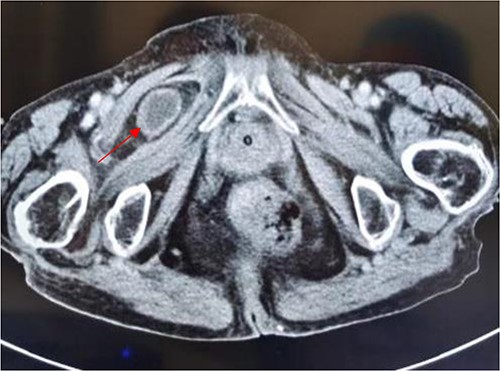

Tumor (indicated by black arrow) on the ascending colon observed during operation.

Laparoscopic exploratory laparotomy and obturator hernia repair were performed. A 4 × 4 cm thick hard tumor was observed in the ascending colon near the liver curve, involving serosa, and the ascending colon was partially blocked. A total of 80 cm away from ileocecum, the intestine entered from the right obturator hernia, causing obstruction and expansion of the proximal intestinal canal, congestion, and edema of the intestinal wall. We aspirated the ascites, loosened the adhesion around the obturator hernia ring, and returned the small intestine back into the abdominal cavity. It was observed that the intestinal wall of the hernia section was ~4 cm, necrotic, and broken, and the intestinal contents were flowing out, the intestinal defect was immediately closed, the abdominal cavity was flushed with normal saline, and the peritoneum at the obturator was intermittently sutured and repaired. A median abdominal incision of ~12 cm was used to cut each layer of the abdominal wall, enter the abdomen, protect the incision, lift out the intestine at the breach, place the aspirator in the intestinal lumen, aspirate large amount of intestinal contents, and temporarily close the breach. The abdominal and pelvic cavities were rinsed again with plenty of normal saline. With the consent of the patient’s family, a double-cavity ileostomy was successfully performed.